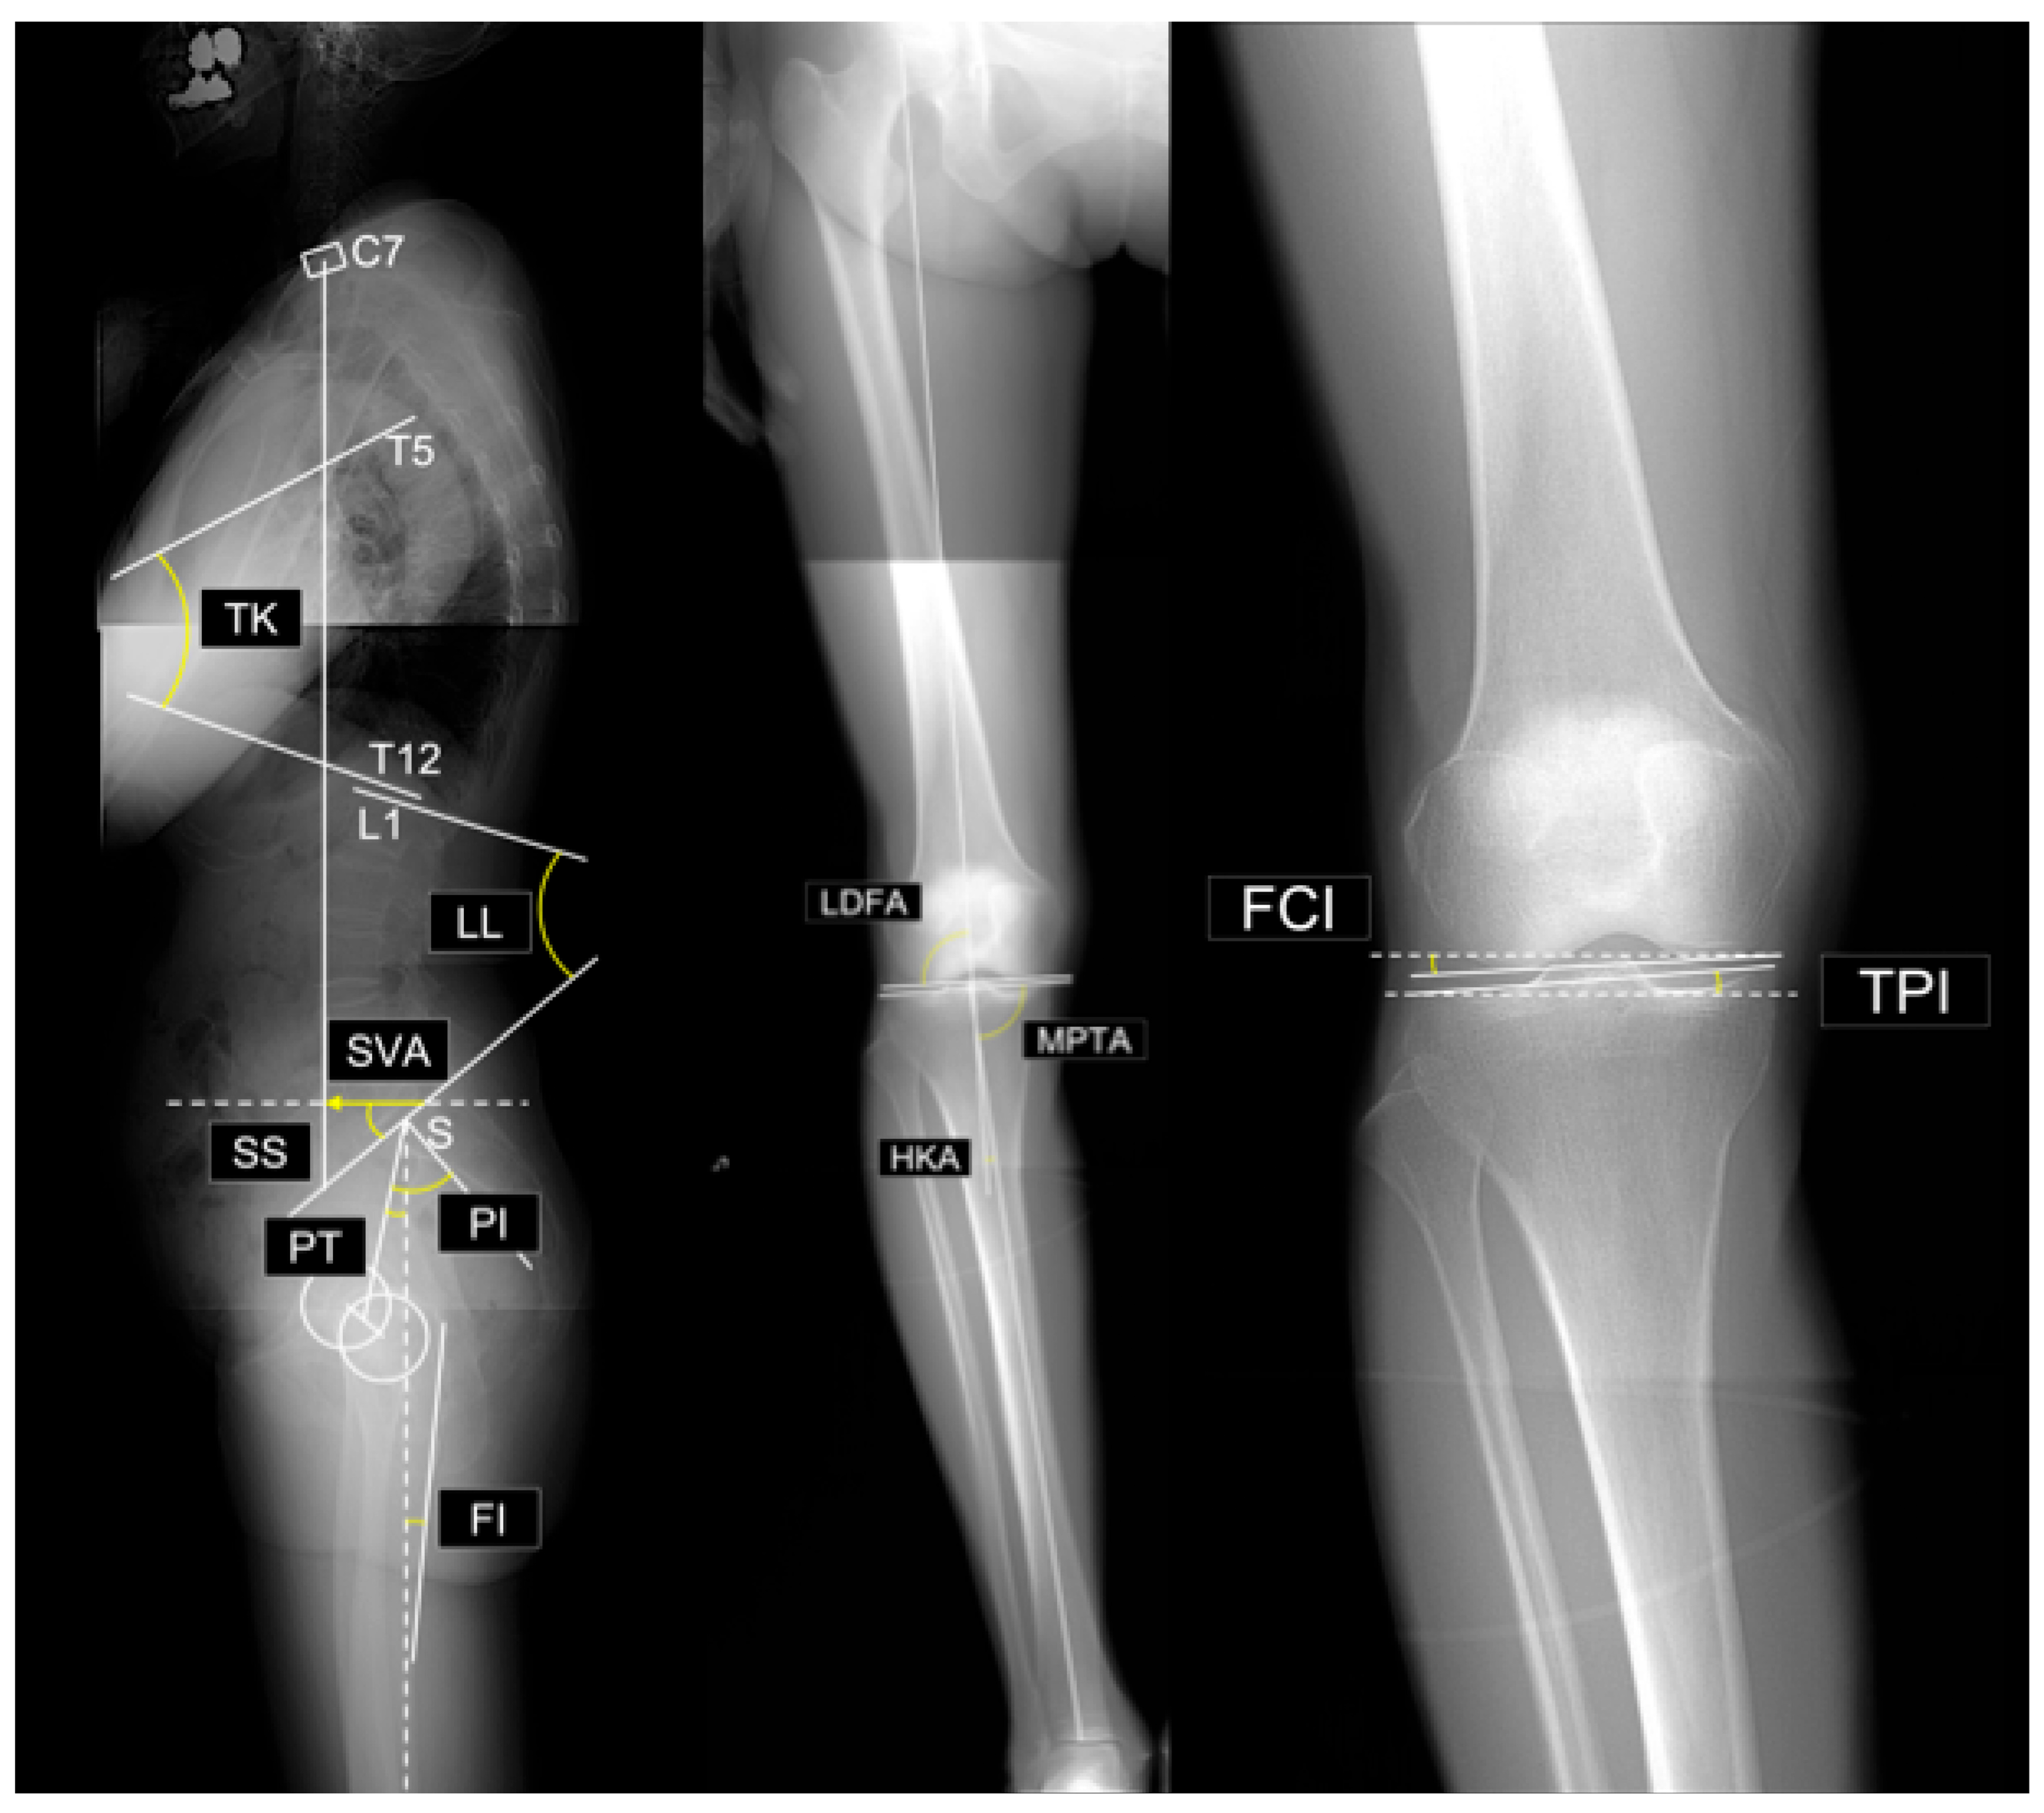

The radiographic parameters (see Figure 1) measured in this study were as follows:

Figure 1. Evaluated radiographic parameters. Abbreviations: SVA, sagittal vertical axis; TK, thoracic kyphosis; LL, lumbar lordosis; SS, sacral slope; PT, pelvic tilt; PI, pelvic incidence; PI–LL, PI minus LL; FI, femoral inclination; LDFA, lateral distal femoral angle; MPTA, medial proximal tibial angle; HKA, hip–knee–ankle angle; FCI, femoral condyle inclination; TPI, tibial plateau inclination.

Lower limb parameters:

• Lateral distal femoral angle (LDFA): The lateral angle between the femoral mechanical axis and distal joint line.

• Medial proximal tibial angle (MPTA): The medial angle between the tibial mechanical axis and proximal joint line.

• Arithmetic hip–knee–ankle angle (aHKA): Defined as MPTA minus LDFA, representing overall lower-limb alignment. Negative values indicate varus alignment.

• Joint line obliquity (JLO): Calculated as the sum of the MPTA and LDFA, reflecting the inclination of the joint line relative to the floor in a bipedal standing position. Values less than 180° indicate the apex distal configuration.

• Hip-knee-ankle angle (HKA): The angle between the mechanical axes of the femur and tibia. A value of 0° represents neutral alignment, and positive values indicate varus alignment.

• Joint line convergence angle (JLCA): The angle formed by the intersection of the distal femoral and proximal tibial joint lines. Positive values indicate a lateral opening.

• Femoral condyle inclination (FCI): The inclination of the femoral joint surface relative to the horizontal plane. Negative values indicate lateral distal inclination.

• Tibial plateau inclination (TPI): inclination of the tibial joint surface relative to the horizontal plane. Negative values indicate medial-distal inclination.